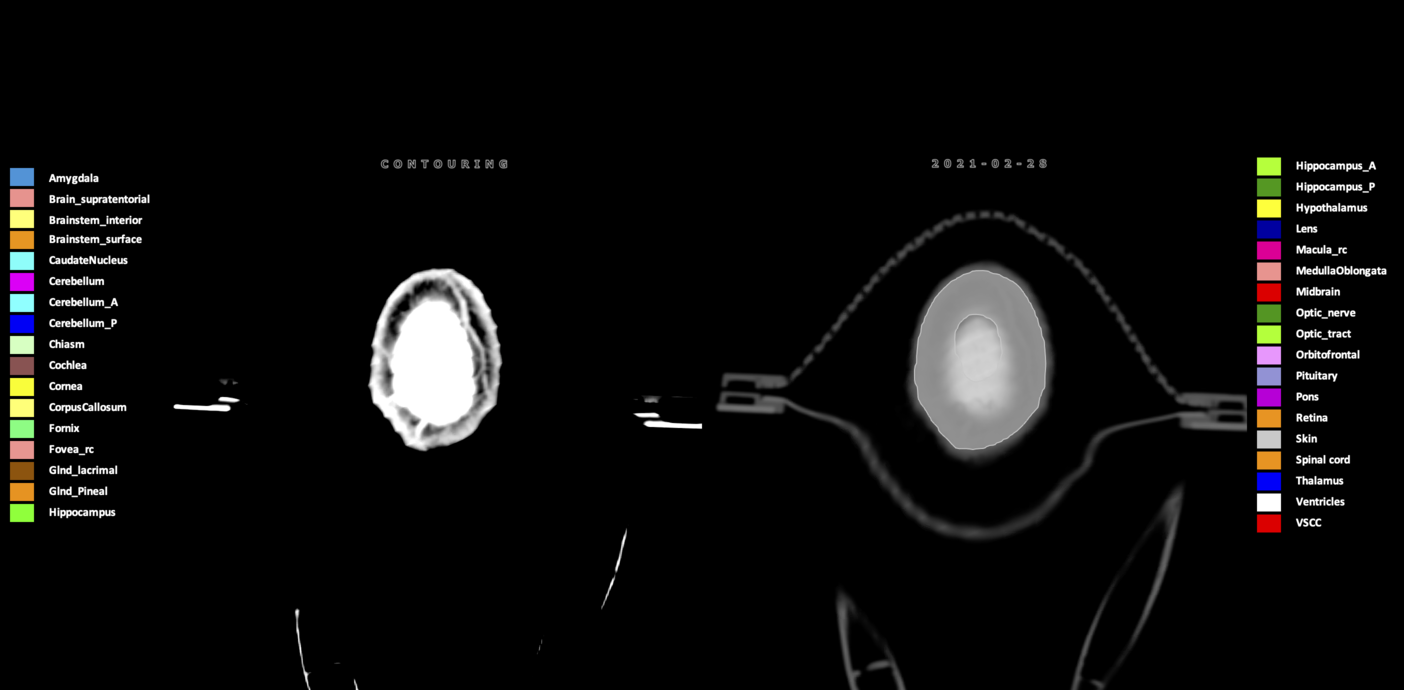

Three-dimensional delineation of the 25 consensus OARs for neuro-oncology are shown on CT (WW/WL 120/40, 3000/600), 3T MR images, (T1Gd, T2FLAIR 1mm) and 7T MR (MP2RAGE 0.7 mm). All are presented in transversal, sagittal and coronal view.